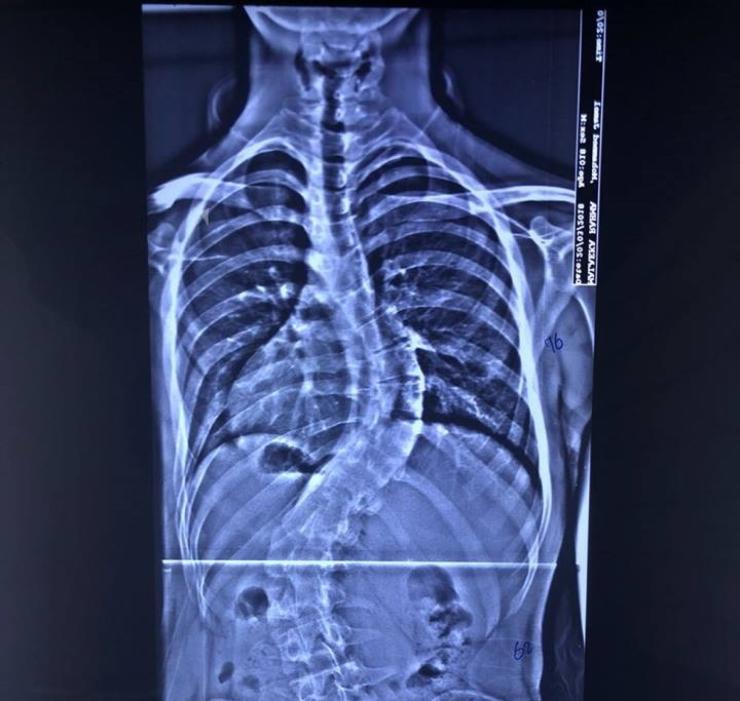

ضمن سلسلة خدماته المجانية .. مستشفى الكفيل يتكفل بعملية مجانية لطفل مصاب باعوجاج العمود الفقريِ

أعلن فريق طبي بمستشفى الكفيل التخصصي نجاحه بعملية تعديل إعوجاج العمود الفقري (سكوليوسز) لطفل بعمر سبعة أعوام، فيما أشاد ذوو الطفل بتكفل المستشفى بإجراء العملية بشكل مجاني. وقال رئيس الفريق الطبيب السوري، د. وائل قاسم اختصاصي جراحة العمود الفقري، ان فريقنا نجح بإجراء عملية لطفل بعمر سبعة أعوام يعاني من اعوجاج العمود الفقري (سكوليوسز). مبيناً "ان العملية إستغرقت قرابة الـ(9) ساعات واجريت بتقنيات طبية حديثة وفرها المستشفى، وإستعاد الطفل إستقامة عموده الفقري بشكل جيد. من جانبه قال والد الطفل ويدعى (م ـ ج)، ان المستشفى تكفل بإجراء العملية لولدي بشكلٍ مجاني بعد أن وجهت مناشدة لإدارته وتمت الإستجابة لي سريعاً. معرباً عن شكره للمستشفى لما يقدمه من خدمات مجانية للمرضى المحتاجين من مختلف محافظات البلاد، ومساهمته بمعالجة المرضى الذين لا يملكون ثمن العلاج وغير قادرين على السفر للعلاج في الدول الإخرى. يذكر أن واردات المستشفى تذهب بالكامل لتمويل خدماتها التشغيلية - ومنها رواتب العاملين - ولرعاية المرضى الفقراء، إذ أن ارتفاع أسعار العمليات هو بسبب ارتفاع سعر الأجهزة المتطورة والتي تضاهي ما موجود عالمياً وهي تتطلب ادامة مستمرة، وهذا يحتاج مبالغ كبيرة. كما أن جميع العمليات التي تجرى في المستشفى يقوم بها أطباء متميزون ومختصون إزاء نسبة معينة من المبلغ الذي يدفعه المريض، وهم من العراقيين والمغتربين والاجانب من ذوي الخبرة والنجاحات العالمية. أما الجزء الثاني من مبلغ العملية الذي يدفعه المريض، فيذهب لتغطية رواتب العاملين والاطباء المقيمين والممرضين، وتغطية مصاريف المستشفى من الكهرباء والماء وخدمة المعامل الخدمية التابعة للمستشفى، وخدمات الجباية الحكومية، إضافة إلى تمويل تذاكر وتأشيرات واقامة وحماية الاطباء الاجانب المستقدمين من الخارج. وما يتبقى من حصة المستشفى يغطي مشروع (اطباء بلا اجور)، الذي يهدف لمساعدة المرضى الفقراء والحشد ومن كل الفصائل، ومشروع (التخفيض) الذي يتكفل إجراء العمليات لفقراء المرضى بشكل مجاني أو بتخفيض الكلفة لنصفها او ثلثها.